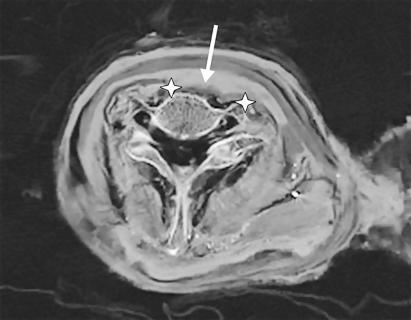

Theo Viện Xác ướp và người tuyết châu Âu (IMI), nơi trực tiếp thực hiện nghiên cứu này thì bằng kỹ thuật chụp cắt lớp vi tính (CT), các nhà khoa học đã phát hiện thấy một vết thương nghiêm trọng ở cổ nhà vua, hậu quả của một vết cắt hoặc do một vật sắc nhọn gây ra.

Ảnh chụp cắt lớp cổ họng Vua Ramesses III.

Trước đây, các nhà khoa học đã tiến hành rất nhiều nghiên cứu để tìm ra bí ẩn về cái chết của vị vua này nhưng đều thất bại, lần này, các nhà khoa học đã tiến hành nghiên cứu 2 xác ướp, một của Vua Ramesses III và một có tên Người đàn ông E (Man E) mà người ta tình nghi là con của Ramisses III. Theo TS. A. Zink - người đứng đầu nhóm nghiên cứu ở IMI thì qua các tài liệu viết bằng giấy cói thời cổ cho thấy, cái chết của Vua Ramesses III là do chính các thành viên hoàng gia gây ra, nhưng hầu như không có sách nào ghi cụ thể về vụ án mạng này, nhất là nguyên nhân trực tiếp gây ra cái chết của nhà vua. Với kỹ thuật chụp cắt lớp CT cho thấy, nhà vua bị sát hại bằng cách cắt đứt cổ họng, khí quản, thực quản và những mạch máu lớn bị cắt lìa làm cho nhà vua chết ngay lập tức. Cũng qua chụp cắt lớp, các nhà khoa học đã tìm ra chính xác các vết thương trên cổ nhà vua, là do bị cắt hoặc do vật kim loại sắc nhọn đâm vào. Ngoài ra, các nhà nghiên cứu còn tìm thấy một chiếc bùa hộ mệnh có hình đôi mắt của vị thần chiến tranh Horus kẹp bên trong cổ họng xác ướp mà người ta tin rằng nó đóng vai trò như là một vị thần may mắn, hộ mệnh cho nhà vua sau khi sang thế giới bên kia. Hoặc cũng rất có thể đây là thủ tục ướp xác của người Ai Cập cổ đại, bởi trong quá trình ướp xác người ta đã cố gắng hồi phục vết thương cho người quá cố càng nhiều càng tốt hoặc cũng có thể dùng cho mục đích chữa bệnh mang màu sắc tâm linh. Ngoài bùa hộ mệnh, người ta còn tìm thấy nhiều vòng cổ khác bên cạnh xác ướp.